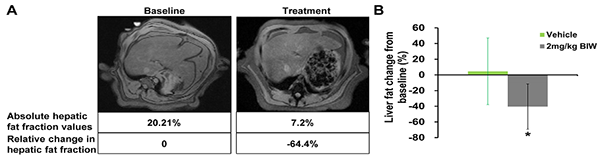

B1344对高脂饮食喂养的食蟹猴脂肪肝的治疗作用

符合入选标准的肥胖食蟹猴接受B1344治疗或对照处理,第69天通过磁共振成像(MRI)测定肝脏脂肪。(A)经每周两次给予2 mg/kg B1344治疗后的猴子肝脏脂肪含量的MRI测量结果;(B)经每周两次给予2 mg/kg B1344治疗后的猴子肝脏脂肪含量的定量测定结果。

李于研究组近期发现FGF21调控肝脏胰岛素抵抗、代谢组织间对话和肝纤维化的机制(Li Y, et al, Gastroenterology, 2014; Gong Q, et al, Hepatology, 2016; Sun Y, et al, Br J Pharmacol, 2018)。为了进一步推进FGF21在NASH适应症方面的临床应用,李于研究组与天士力生物以及昆明科灵生物科技有限公司通力合作,团队成员崔奥媛、李剑、纪少珲等比较了该药物与天然FGF21对其人源和猴源受体复合物FGFR1c/βKlotho的激活效果,发现与FGF21相比,B1344对下游通路具有更好的激活能力。随后,研究人员选择了高脂饮食喂养的食蟹猴、蛋氨酸胆碱缺乏饮食喂养的小鼠构建NASH模型,来验证B1344对NASH的治疗效果。在高脂饮食喂养的食蟹猴模型中,研究人员将符合入组标准并经过训练的猴子随机分成五组,以皮下注射的方式每周两次给予高、中、低剂量的B1344或每周一次给予高剂量B1344,对照组则注射等量生理盐水。令人兴奋的是,B1344具有良好的减轻肝脏脂质沉积和纤维化的作用。核磁共振结果显示,经每周两次给予2 mg/kg B1344治疗后的猴子,肝脏脂肪含量降低了40%;同时,在治疗11周后,利用肝穿刺的方法获得了猴子的肝脏组织标本,病理切片表明B1344确实能有效缓解脂质沉积和纤维化水平,伴随中性粒细胞及巨噬细胞的浸润程度减少。此外,肥胖猴子在接受B1344治疗后,体重、空腹血糖、血脂谱及胰岛素敏感性也得到了显著的改善,而DEXA测定显示骨密度未见明显改变。同样,在小鼠模型中,B1344干预两周即能有效缓解NASH症状,包括脂质沉积、肝小叶炎症及肝细胞气球样变,并降低了纤维化程度及肝酶水平,减少促炎及促纤维化相关基因表达。这些结果表明,在高等非人灵长类动物与啮齿类动物模型中,B1344均能有效改善NASH症状,缓解单纯脂肪肝向脂肪性肝炎的发展进程。